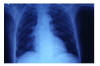

APR Insuficiencia cardiaca